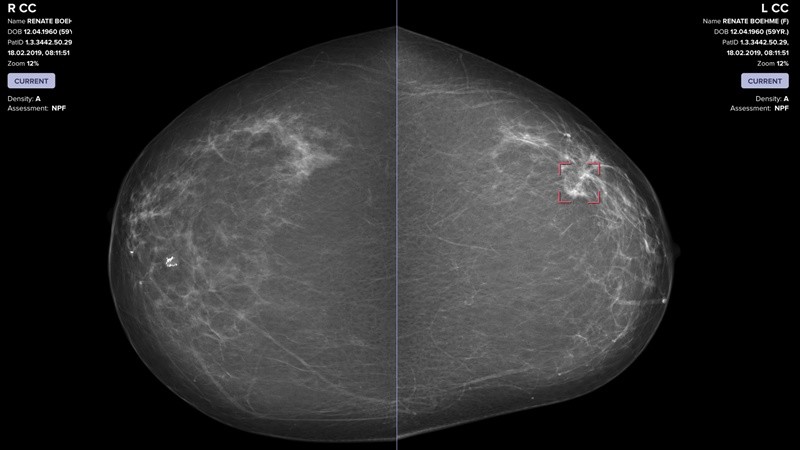

Un ejemplo concreto de este antes y después en la historia de la salud se encuentra en la detección del cáncer de mama. Aquí, los algoritmos de aprendizaje automático demostraron una rigurosidad extraordinaria para identificar señales microscópicas que indican un comportamiento celular anormal. Un estudio realizado en Suecia entre casi 106.000 mujeres de entre 40 y 74 años reveló que el screening asistido por IA detectó un 29% más de casos de cáncer de mama en comparación al método convencional de doble lectura por radiólogos. Además, este aumento en la detección incluyó un 24% más de tumores invasivos en etapa temprana y un 51% más de lesiones precancerosas, factores decisivos para mejorar el pronóstico y evitar tratamientos más agresivos.

La interpretación de imágenes es tal vez una de las aplicaciones más maduras y visibles de la IA en la medicina. Los algoritmos de aprendizaje profundo, una rama más avanzada del aprendizaje automático, ya demostraron que pueden analizar radiografías, tomografías computarizadas, resonancias magnéticas y hasta muestras de tejido con una velocidad y precisión superiores a los procedimientos tradicionales, llegando incluso hasta elaborar informes detallados.

Un estudio publicado en junio de 2025 mostró cómo la incorporación de inteligencia artificial generativa en tiempo real dentro del sistema de imágenes permitió que los informes se redactaran automáticamente mientras el radiólogo analizaba los estudios, produciendo un borrador que luego era revisado por el especialista. Esta integración no solo mantuvo la calidad del diagnóstico, sino que además redujo drásticamente los tiempos de trabajo, con mejoras en la eficiencia que llegaron hasta el 40%. Además, esta herramienta incluye funciones de triaje automatizado, de modo que si el sistema detecta una condición grave, la marca y la compara con el historial del paciente para alertar al radiólogo de inmediato, incluso antes de que este haya revisado las imágenes.